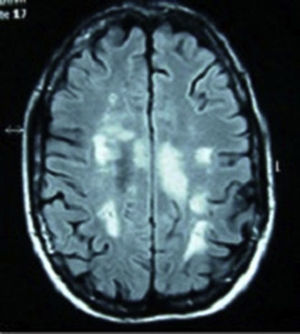

Caso 3. Mujer de 22 años, caucásica, diagnosticada de LES a los 15 años sobre la base de poliartritis, afectación cutánea y mucosa, linfopenia, ANA y anticuerpos anti-ADN positivos a títulos altos. Realizada biopsia renal por alteraciones urinarias persistentes se objetivó nefropatía lúpica tipo iv, y se inició terapia con ciclofosfamida, prednisona e hidroxicloroquina. Acudió con dolor lumbar, disuria y astenia, con instauración progresiva de parestesias en el hemiabdomen derecho y paresia de los miembros inferiores. La analítica mostró un recuento leucocitario de 30.000×109 (sin desviación izquierda), velocidad de sedimentación globular 58mm/h, proteína C reactiva 6,41mg/dl y ácido láctico 1,10 mmol/l. Los repetidos análisis de hemocultivos y urocultivo resultaron negativos. El estudio inmunológico mostró ANA positivos 1/320, anticuerpos anti-ADN de 167 U/ml, con anticuerpos antifosfolípidos negativos. La RM de columna (fig. 2) se informó como mielitis de gran segmento a nivel de la médula espinal dorsal. En la RNM de cráneo se objetivó cambios en la señal del hemisferio cerebeloso izquierdo que pudieran estar en relación con vasculitis lúpica a ese nivel, mostrando señal difusa hiperintensa en FLAIR y T2. No se usó gadolinio por negación de la paciente. En la punción lumbar se obtuvo un líquido transparente y normotenso, con 58 mm3, 80% polimorfonucleares, 20% linfocitos, glucosa 127mg/dl, proteínas 1.015mg/dl y lactato deshidrogenasa 216 U/l. En la tinción de Gram del líquido cefalorraquídeo no se observaron bacterias y el cultivo para hongos y CO2 resultó negativo. Se añadieron al tratamiento bolos de metilprednisolona y 48 h después comenzó con crisis comiciales resistentes a tratamiento con valproico. Se decidió su ingreso en la Unidad de Cuidados Intensivos, donde se inició tratamiento con fenitoína y midazolam para el control de las convulsiones junto a tuberculostáticos, cefalosporina y aciclovir de forma profiláctica. Tras un pico febril presentó un brusco deterioro neurológico, con Glasgow de 8/15. La tomografía computarizada de cráneo de control mostró un edema cerebral masivo y generalizado, con borramiento de surcos y cisternas, no diferenciándose entre la sustancia blanca y la gris. Tras la administración de contraste apenas existió circulación intracraneal, con signos de isquemia generalizada. En bradicardia y aberración del complejo desencadenó en paro cardiorrespiratorio.

Respecto al diagnóstico, la RM es su prueba determinante. Los estudios muestran anormalidad de la señal con hiperintensidad en T2, realce con gadolinio y edema del cordón medular. No existen imágenes específicas según la etiología, si bien múltiples pequeñas lesiones parecen indicativas de LES, mientras que lesiones muy extensas y anormalidades en varios niveles son más indicativas de vasculitis12. En la RM cerebral podemos encontrar lesiones desmielinizantes en T2/FLAIR, con marcada afectación, como en nuestro caso 1. En el estudio del líquido cefalorraquídeo se puede observar inflamación del cordón medular, con pleocitosis o valores elevados de IgG. En el estudio inmunológico básico podemos encontrar los anticuerpos antimielina (que pueden predecir la evolución de un síndrome clínicamente aislado hacia la esclerosis múltiple) y los anticuerpos antiacuaporinas 4. La recurrencia de la MT se ha asociado a la existencia de anticuerpos anti-Ro/SSA13. Sin embargo, es precisamente nuestro caso de SS con episodios de repetición (caso 2) el que no presenta anticuerpos anti-Ro/SSA ni anti-La/SSB, basándonos para su diagnóstico en criterios clínicos e histológicos.